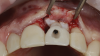

(3.) The crown was removed, and a partial thickness flap was reflected using a papilla-sparing incision design, which revealed that the implant was positioned too far facially and that its body was visible through a very thin layer of bone.

Figure 3

(4.) The crown was removed, and a partial thickness flap was reflected using a papilla-sparing incision design, which revealed that the implant was positioned too far facially and that its body was visible through a very thin layer of bone.

Figure 4

The patient in this case had undergone implant therapy at the site of tooth No. 9 and was restored with a cement-retained restoration more than 5 years prior. At presentation, the site demonstrated a peri-implant soft-tissue dehiscence that extended approximately 3-mm apical to the gingival margin of tooth No. 8. Thin and erythematous marginal tissue was evident at the zenith (Figure 2). The crown was removed, and a partial thickness flap was reflected using a papilla-sparing incision design. This revealed that the implant was positioned too far facially and that its body was visible through a very thin layer of bone (Figure 3 and Figure 4). The first objective of treatment was to minimize the facial extent of the emerging abutment and crown. To accomplish this, the facially positioned abutment and implant crown margin were both recontoured. The second treatment objective was to provide additional supracrestal soft tissue that would more adequately maintain the peri-implant margin. The tuberosity was selected as a donor site due to its dense, high-quality connective tissue, low propensity for shrinkage, and association with minimal patient discomfort. Once the graft was secured (Figure 5 through Figure 7), the flap was coronally positioned (Figure 8). After a healing period of 2 weeks, the margin of tooth No. 9 exhibited an ideal position in relation to its contralateral counterpart and demonstrated increased soft tissue thickness (Figure 9). Three months postoperatively, further healing had improved the esthetics and the position of the margin had been maintained (Figure 10).